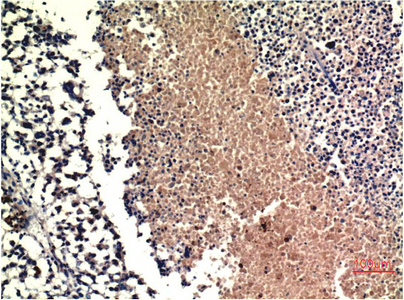

IHC-P analysis of human lung carcinoma tissue using GTX34151 PTEN antibody [9E8].

Dilution : 1:200